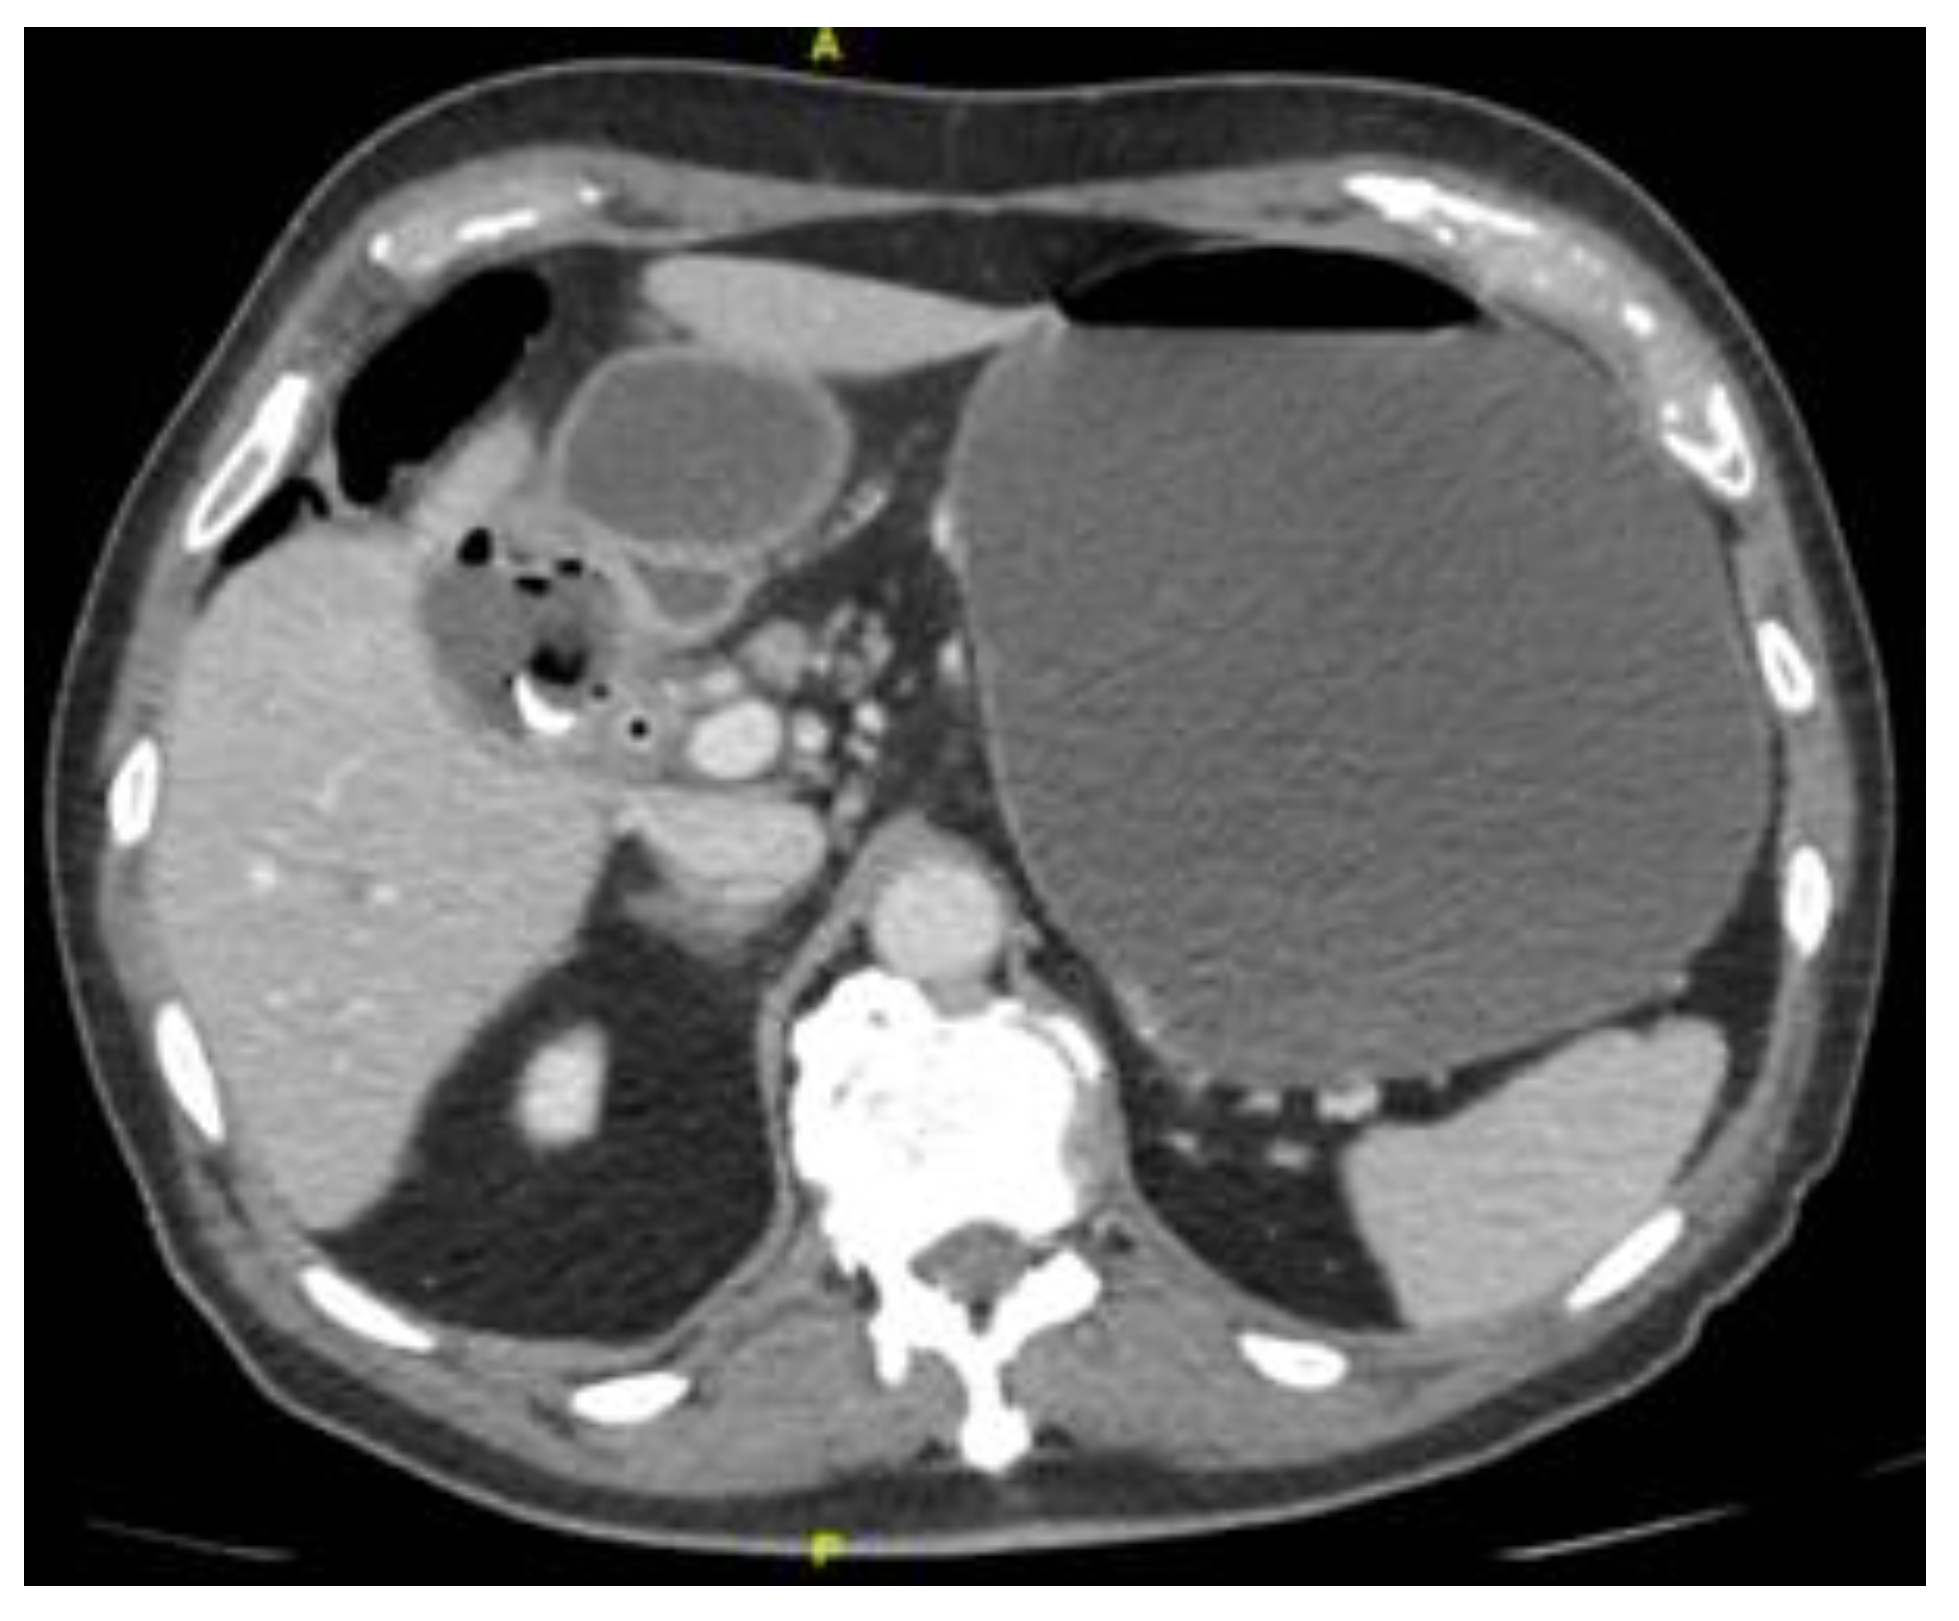

Figure 5 and Figure 6 Subsequent computed tomography with intravenous contrast material confirmed pneumobilia with direct visualization of a tract between the gallbladder and the duodenum and a 25 mm gallstone impacted in the duodenal bulb (long arrow) causing gastric distention so diagnosis of cholecystoduodenal fistula was made. Bouveret’s syndrome is characterized by gastric outlet obstruction (GOO) secondary to cholecystoduodenal fistula. [1,2] Fistula formation is favoured by the long history of cholelithiasis, the repeated episodes of acute cholecystitis, the large size of the gallstones (2–8 cm), the female gender and advanced age ( > 60 years ). Morbidity and mortality rates are high, estimated at 60% and 12%–30% respectively, due to the advanced age and the comorbidities of the patients. [3] Patients usually present with non-specific signs and symptoms of GOO, including nausea and vomiting in 87%, abdominal pain in 71%, hematemesis in 15%, weight loss in 14% and anorexia in 13%. [4] The radiologic features of gallstone ileus are the classical Rigler’s triad that consists of pneumobilia, dilated small bowel and an ectopic gallstone. [5] A plain abdominal X- ray is diagnostic in about 50% of cases and may demonstrate intestinal obstruction, pneumobilia, an ectopic gallstone, alteration in the position of the previously observed stone or two air fluid levels in the right upper quadrant secondary to air in the gall bladder. [6] US may show the gallstone sufficiently large to be apparent. The fistula may also be visualized if filled with fluid or air. Pneumobilia and a dilated stomach may also be seen with US. [7,8] CT is the best imaging technique used to search for Rigler’s triad that is specific to gallstone ileus and with it’s 93% sensitivity, 100% specificity, and 99% accuracy is needed for definitive diagnosis. [9] Up to 20% of the gallstones may be isoattenuating when MRI is indicated because it detects Rigler’s triad in nearly all cases where it was present. [10]

Figure 5. Computed tomography.

Preprints 107205 g005

Figure 6. Computed tomography.

Preprints 107205 g006